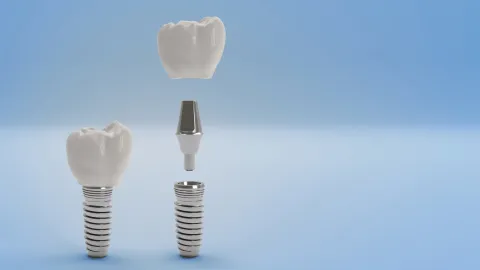

Welkom bij Sinident, uw tandartspraktijk in Sint-Niklaas, onder leiding van Lut Geers, gespecialiseerd in parodontologie en implantologie. Wij bieden volledige tandheelkundige zorg, van algemene tandheelkunde tot esthetiek, implantaten en chirurgie.

Specialisaties